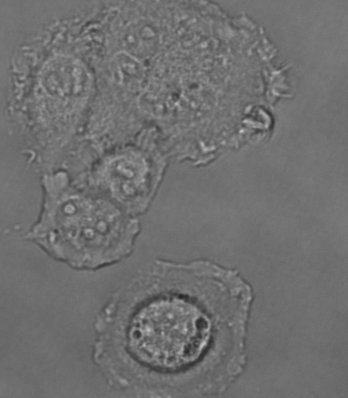

MCF-7细胞怎么是这个样子呢?

大家好,最近在养MCF-7细胞,刚拍完照片,发现细胞状态好像不对!

求鉴定?细胞是不是死了啊?

20倍

细胞要是漂的或半悬浮就是死了。这上面看不出来。从图上看细胞状态不好,正常应该成呈梭形或长条状,细胞排列规整,细胞间隙明显,视野干净,透亮。图中细胞器肿胀,应该活不了太久。